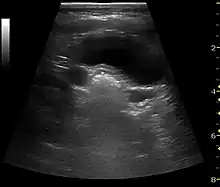

Complex cysts can have membranes dividing the fluid-filled center with internal echoes, calcifications or irregular thickened walls. The complex cyst can be further evaluated with Doppler US, and for Bosniak classification and follow-up of complex cysts, either contrast-enhanced ultrasound (CEUS) or contrast CT is used (Figure 6). The Bosniak classification is divided into four groups going from I, corresponding to a simple cyst, to IV, corresponding to a cyst with solid parts and an 85–100% risk of malignancy.[1] In polycystic kidney disease, multiple cysts of varying size in close contact with each other are seen filling virtually the entire renal region. In advanced stages of this disease, the kidneys are enlarged with a lack of corticomedullary differentiation (Figure 7).[1]

Figure 9. Renal cell carcinoma with both cystic and solid components located in the cortex. Measurement of tumor on the US image is illustrated by '+' and a dashed line.[1]

A solid renal mass appears in the US exam with internal echoes, without the well-defined, smooth walls seen in cysts, often with Doppler signal, and is frequently malignant or has a high malignant potential. The most common malignant renal parenchymal tumor is renal cell carcinoma (RCC), which accounts for 86% of the malignancies in the kidney. RCCs are typically isoechoic and peripherally located in the parenchyma, but can be both hypo- and hyper-echoic and are found centrally in medulla or sinus. The lesions can be multifocal and have cystic elements due to necrosis, calcifications and be multifocal (Figure 8 and Figure 9). RCC is associated with von Hippel–Lindau disease, and with tuberous sclerosis, and US has been recommended as a tool for assessment and follow-up of renal masses in these patients.[1]